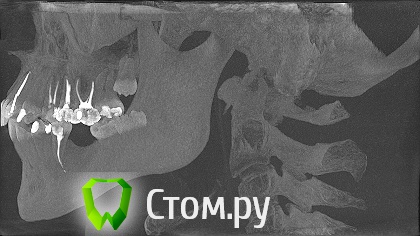

melania Опубликовано 13 мая, 2014 Поделиться Опубликовано 13 мая, 2014 зуб 15 лет назад депульпированный. пломба составляла большую часть зуба. со временем разрушилась, осталась одна стенка и то искусственного материала. сейчас при посещении стоматолога слышу что зуб резецированный (?) . никаких операций не было. сам корень синий (вижу через десну просвечивает.\ принято решение перепломбировать каналы и поставить вкладку +коронку. вопросы собственно -1. насколько это актуально, не разрушится ли все в ближайшее время.2. планируются брекеты (проблемная сторона противоположная.) ортодонт считает что этот зуб не помешает ситуации. и на него брекет ставить не будет. не вызовет ли подвижность соседних зубов при перемещении проблем? на фото зуб до перепломбировки канала. на сегодняшний день уже запломбировали заново, потому что в верхушке канала просматривалась пустота. Ссылка на комментарий

Гарриевич Опубликовано 14 мая, 2014 Поделиться Опубликовано 14 мая, 2014 скорее всего "резорциненый" собственно о каком зубе речь?Выкладывайте снимки после лечения. О 25.По мне так нормально пролечен, по этим снимкам Ссылка на комментарий